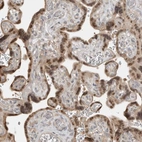

Immunohistochemical staining of human placenta shows nuclear positivity in trophoblastic cells.